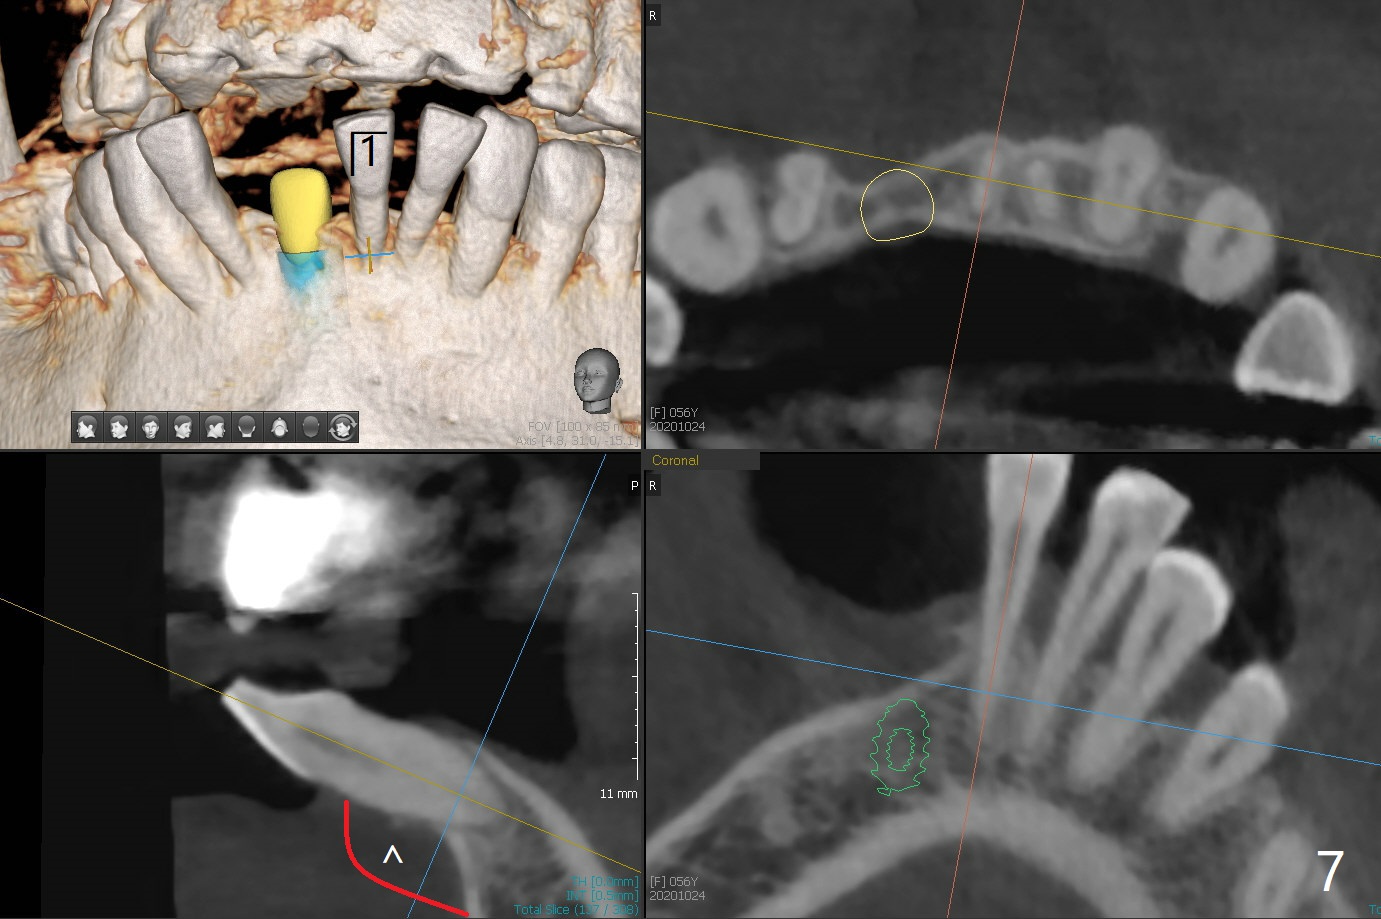

56岁女牙周炎,失去右上6,7以及右下1,后者缺牙间隙特别宽,其余切牙往颊侧移位(flare,病人不愿意拔除,图一)。右上植牙修复后(图二,三),下前牙种植(图四,五(选择窄植体)),建立正常覆盖,同时在邻近切牙唇侧植骨(图七,八:红线)。四-六个月后做局部矫正:使用植牙作为支抗将颊侧移位的前牙(牙冠)往舌侧推移(图七,八:蓝箭头),而牙根可能往唇侧移位(图六:红箭头),所以事先植骨(图七,八:红线)重要。矫正后3-3舌侧放置钢丝树脂固定。Jennifer: #25 implant and crown should be lingualized, as compared to the rest of the lower incisors (flared). After osteointegration, ortho will be conducted to correct the flaring using #25 implant as an anchor.